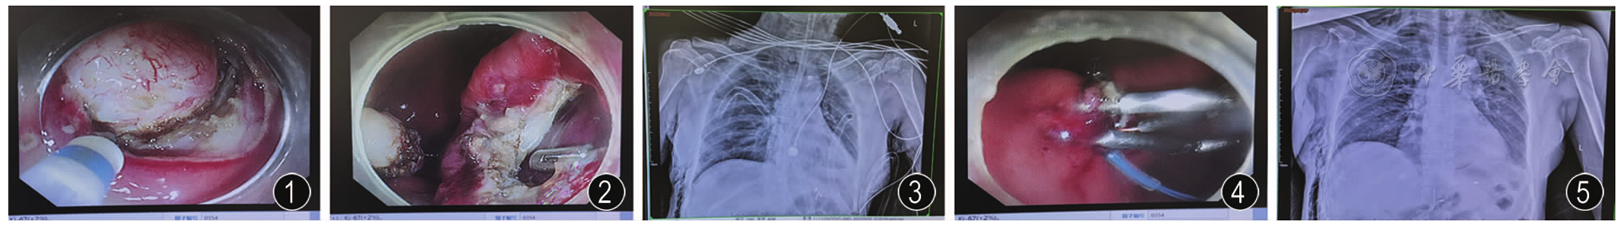

内镜下胃间质瘤挖除术致穿孔和气胸急救一例

患者女性,64岁,主因外院查体"发现胃体病变2个月余"于2022年9月20日入院。2022年7月10日患者在外院行胃镜检查显示:胃体前壁下部近胃角可见一大小约2.5 cm×3 cm黏膜隆起,超声提示病灶起源于固有肌层低回声病变,诊断:胃间质瘤。既往身体健康。查体:体温36.5 ℃,心率70次/min,呼吸18次/min,血压130/70 mmHg(1 mmHg=0.133 kPa)。患者心肺影像及功能检查正常。患者入院后完善相关检查,结果显示无手术禁忌,签署术前知情同意书后,择期行内镜下黏膜肿物挖除术(endoscopic submucosal excavation,ESE)治疗。

图5 治疗后胸部X线片显示胸腔积气减少,钛夹在位。